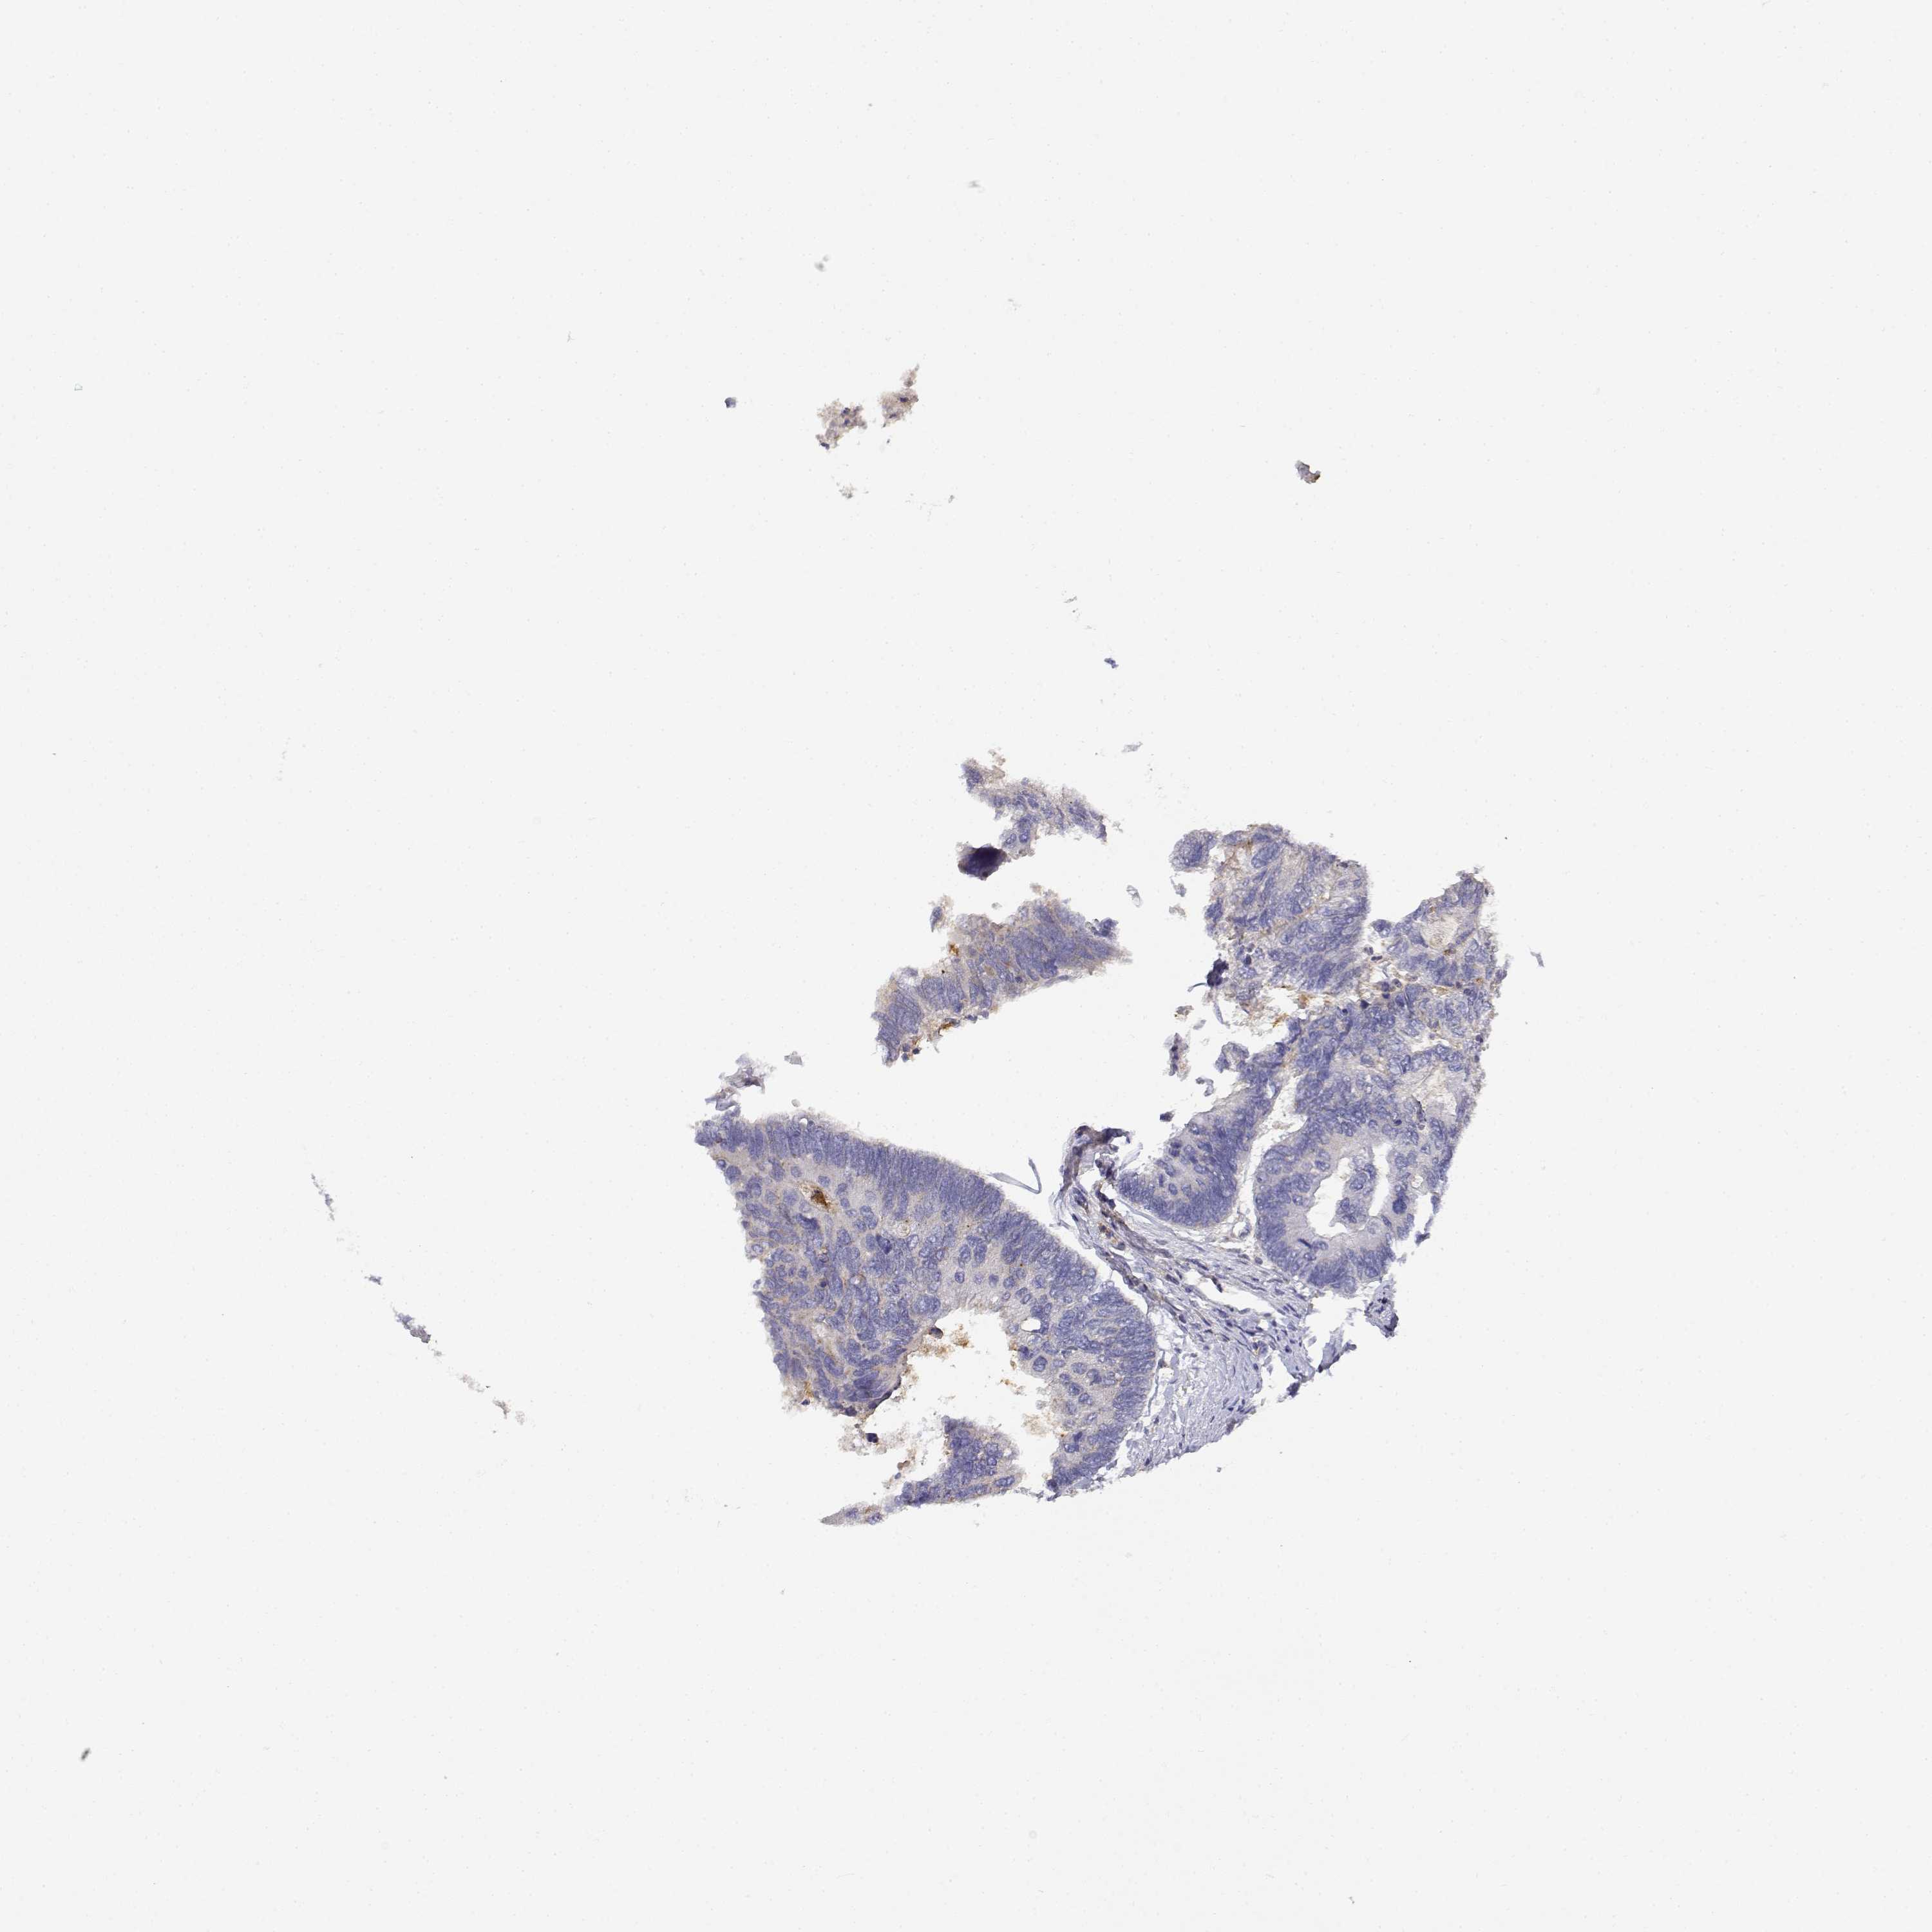

Colorectal cancer

Human cancer

Rectum adenocarcinoma